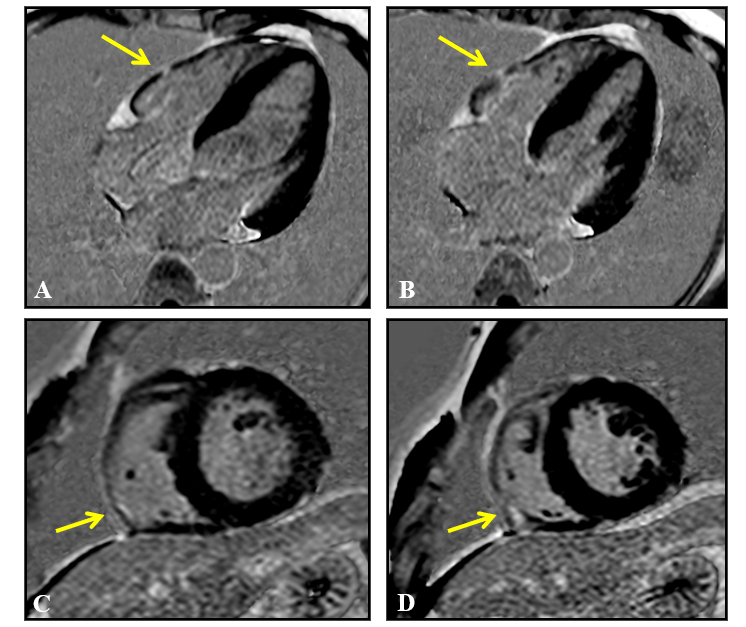

Figure 6 Cardiac magnetic resonance imaging, late gadolinium enhancement sequences, 4 chambers (A and B) and short axis (C and D), showing areas of pathological late enhancement in the myocardium of the inferior-lateral segment of the right ventricular free wall (arrows), without associated left ventricular involvement.